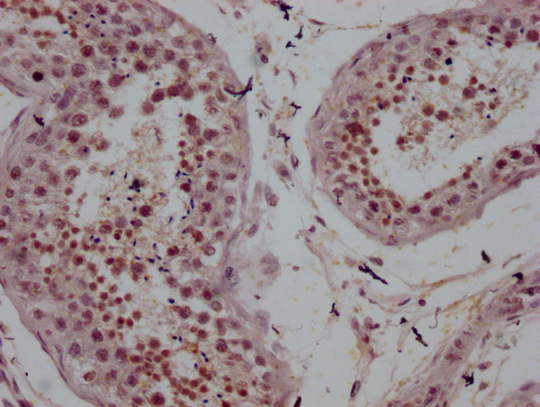

Human liver cancer

1:100